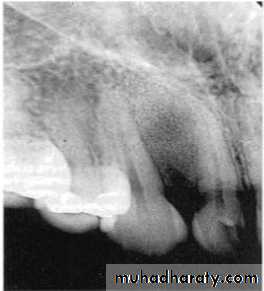

Examination of bone:

Height of alveolar bone

Crest relative to teeth

Loss of height-more than 1.5 mm periodontal disease

Lamina dura + PDL space + tooth roots

Carcinoma erosion of alveolar crest & ill defined borders.